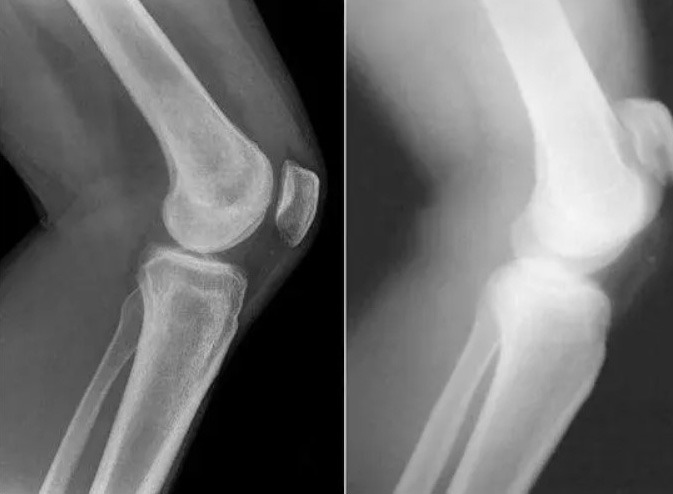

Femme de 54 ans. Son articulation est entièrement restaurée. La durée du traitement : 14 jours :

Traitement de l'articulation de la hanche d'un patient âgé de 44 ans. La douleur atroce qui a torturé le patient pendant 2 ans, a été complètement guérie :

Restauration de l'articulation du coude. Patiente, 31 ans. Durée du traitement par la Voralis Сonfort : 12 jours. Son articulation est entièrement restaurée :